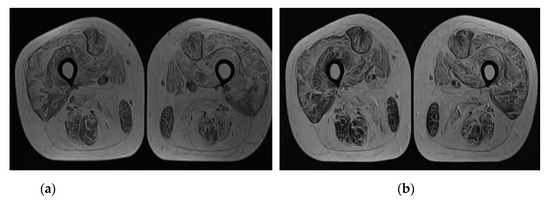

Sarcotubular Myopathy Due to Novel TRIM32 Mutation in Association with Multiple Sclerosis

Azerbaijani 28-year-old female showed weakness (MRC (Medical Research Council Scale for Muscle Strength) grade 4 in the proximal part of the upper and MRC grade 2–3 in the lower extremities), difficulty in stair lifting, positive symptom of Hoover’s rising, «waddling gait», decline deep [...] Read more.

Azerbaijani 28-year-old female showed weakness (MRC (Medical Research Council Scale for Muscle Strength) grade 4 in the proximal part of the upper and MRC grade 2–3 in the lower extremities), difficulty in stair lifting, positive symptom of Hoover’s rising, «waddling gait», decline deep reflexes symmetrical, lack of surface reflexes, positive Babinsky’s reflex on the right, urinary incontinence during sneezing, prolonged walking and exercise from puberty. Additional methods made it possible to identify minor violations of conduction of the left ventricle, electromyography signs of primary muscular disease with predominant involvement of the proximal muscles of the lower extremities, elevation of serum creatine kinase (746.81 U/l), active foci of demyelination in the left frontal lobe, intrathecal synthesis of oligoclonal IgG bands (type 2) in cerebrospinal fluid, atrophy and fatty degeneration of all muscles of the shins, homozygous Variant of Uncertain Significance (VUS) c.1855C > T (p.Pro619Ser) in TRIM32 gene and heterozygous VUS c.2300C > G (p.Thr767Arg) in KIF5A, c.2840G > A (p.Arg947Lys) in MYH2, c.1502G > C (p.Gly501Ala) in POMT1 genes. Comparison of the phenotypes of the mutations that have been identified with the clinical picture of the patient suggests that VUS c.1855C > T (p.Pro619Ser) in the TRIM32 gene can be pathological. Summarizing, it can be argued that the cause of the identified disorders is a homozygous variant c.1855C > T (p.Pro619Ser) in TRIM32 gene that causes LGMDR8 in a patient with MS. Full article

Figure 1